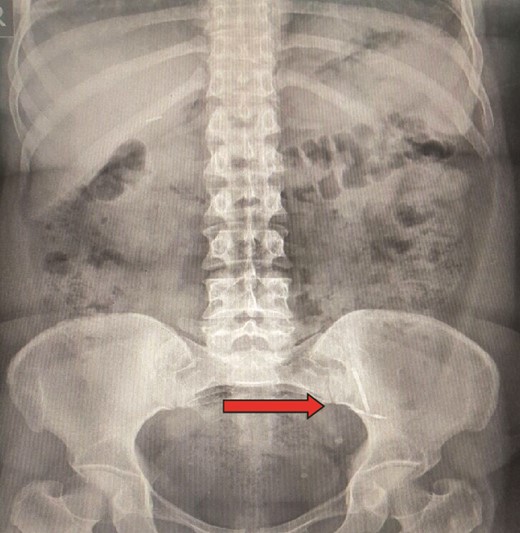

An abdominal radiograph was performed, revealing a foreign body was seen in the left lower abdomen area (Fig. 1).

Abdominal radiograph showing presence of a foreign body in the left lower abdomen.